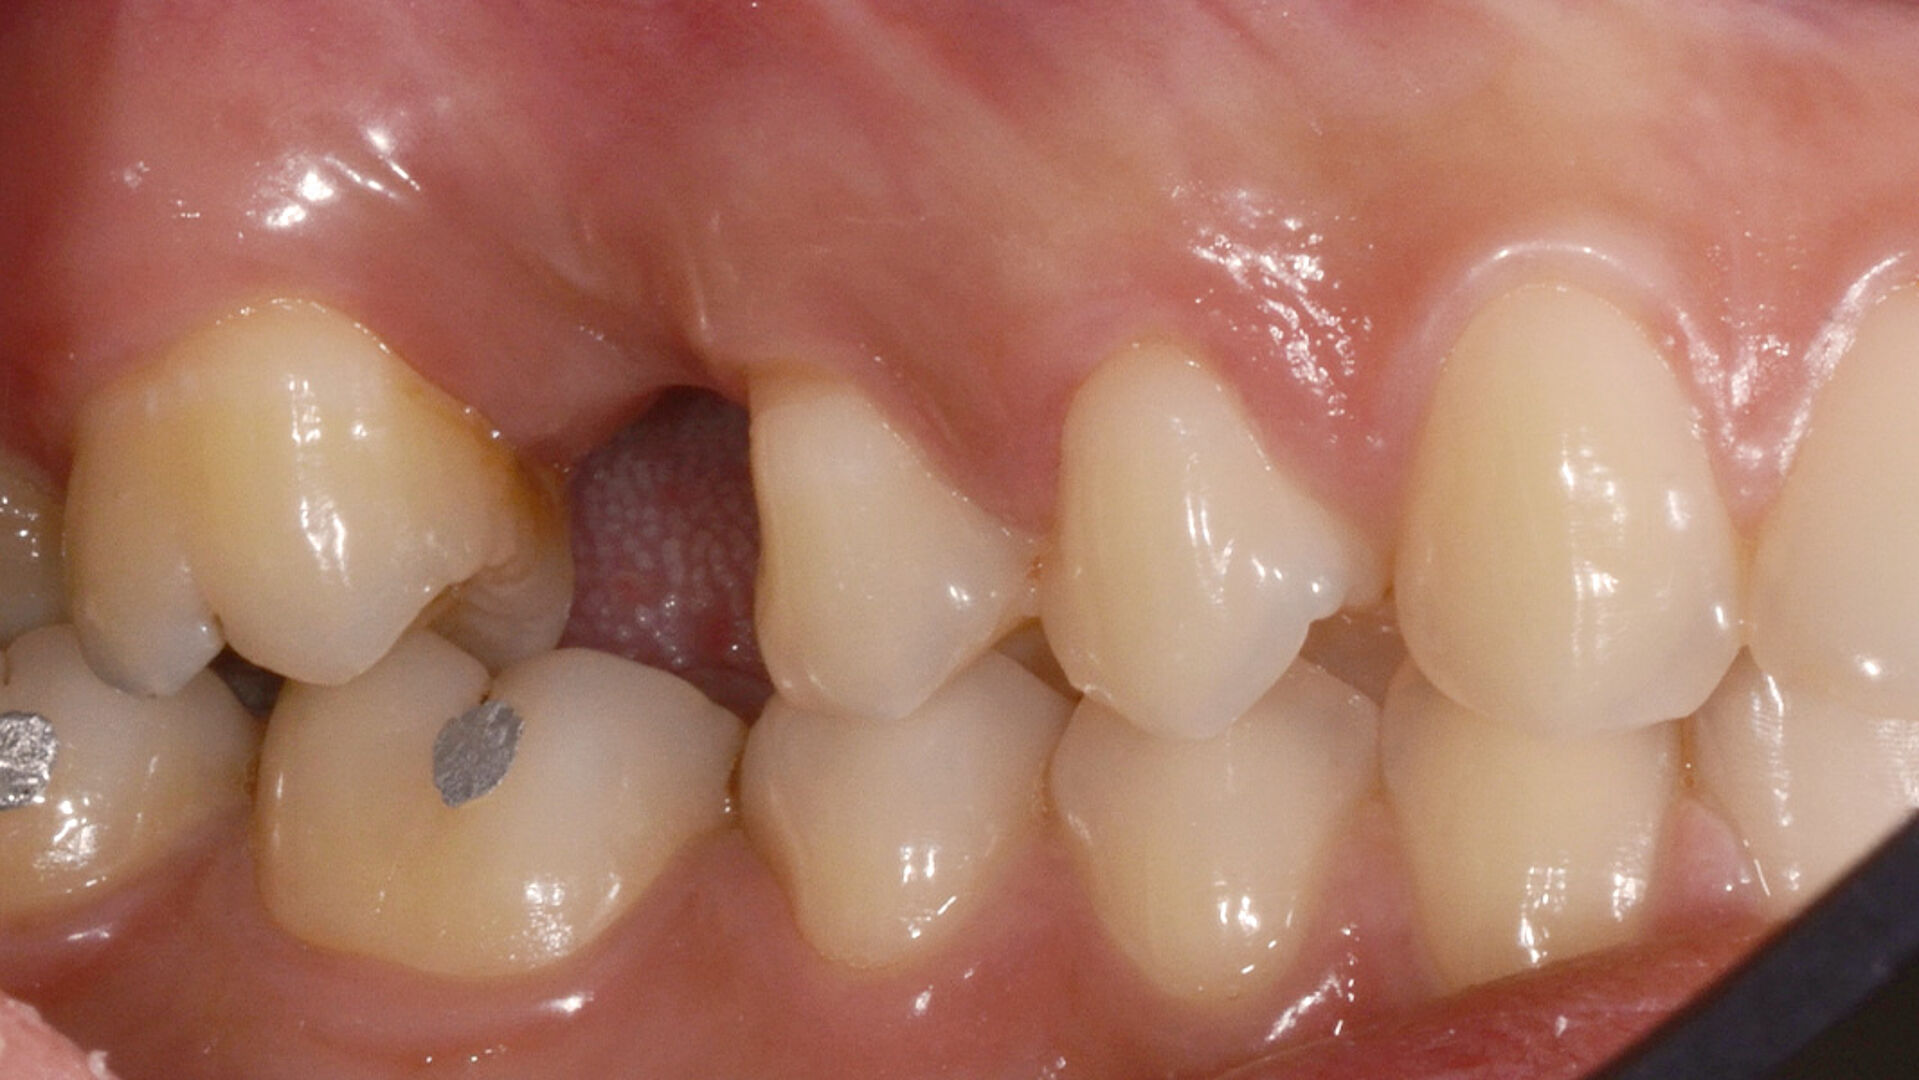

Die transgingivale Einheilung dentaler Implantate ist ein wissenschaftlich gut untersuchtes und klinisch erfolgreiches Verfahren. Für die transgingivale Einheilung sollten die Implantate primärstabil inseriert werden, nur kleine Hartgewebeaugmentationen notwendig sein und ausreichend stabiles Weichgewebe vorliegen. Um in Fällen mit Augmentationsbedarf das iSy Implantatsystem verwenden zu können – ohne die Implantatbasis demontieren zu müssen – bietet das iSy System Implantate mit gestecktem Einbringpfosten an. Nach gedeckter Einheilung und Freilegung des Implantats können drei verschieden breite Gingivaformer eingebracht und im Anschluss sowohl eine digitale als auch konventionelle Abformung durchgeführt werden. Die entsprechenden Abformpfosten und Esthomic Abutments gibt es ebenfalls in drei verschiedenen Emergenzprofilen, welche formkongruent zu den Gingivaformern sind. Im folgenden Fall wurde ein geringes bukkales Knochendefizit mit einem Gemisch aus Eigenknochen und PRF (Plättchenreiches Fibrin) augmentiert und das Weichgewebedefizit mit einer azellulären dermalen Matrix (NovoMatrix/ BioHorizons) aufgebaut.

Für den langfristigen Erhalt einer Implantatversorgung müssen unterschiedliche Entscheidungsfaktoren gegeneinander abgewogen werden. So spielen die anatomischen Voraussetzungen eine ebenso große Rolle wie die Wahl der prothetischen Versorgung. Doch auch die Wünsche der Patienten in Bezug auf Ästhetik und Funktion ihres späteren Zahnersatzes in Abhängigkeit ihres zur Verfügung stehenden Budgets gilt es zu berücksichtigen. Nach Abwägung all dieser Kriterien muss die Entscheidung für den richtigen Implantationszeitpunkt gewählt werden. Trotz des Trends zu Sofortversorgungsprotokollen ist die Spätimplantation im Seitenzahnbereich das risikoärmste Implantationsverfahren in Bezug auf den Zeitpunkt des Eingriffs, denn der Kieferknochen bekommt Zeit, um nach dem Zahnverlust auszuheilen und die Alveole mit Knochengewebe zu durchsetzen. Falls eine Socket Preservation oder aufgrund eines defizitären Kieferknochens eine umfassende Augmentation nach der Extraktion erforderlich sind, kann sich die durchschnittliche initiale Heilungsphase von zirka drei Monaten auf sechs oder mehr Monate verlängern. Nach erfolgter Regeneration des Kieferknochens und des Weichgewebes sind die besten Voraussetzungen für eine komplikationslose Implantation geschaffen.

Ein teilweiser Zahnverlust im Seitenzahnbereich kann zu erheblichen funktionellen Defiziten führen, insbesondere bei jungen Patienten kann er auch ästhetische Probleme verursachen. Störungen des Kiefergelenks (TMJ) treten vor allem dann auf, wenn der Verlust der vertikalen Dimension und die Zahnwanderung nicht frühzeitig behandelt werden. Die Pneumatisierung der Kieferhöhle und der vertikale Knochenabbau im Seitenzahnbereich werden hauptsächlich durch eine nicht behandelte partielle Zahnfehlstellung im Seitenzahnbereich verursacht. In Fällen, in denen die Menge an krestalem Restknochen sehr gering ist, kann die Möglichkeit, den nativen krestalen Knochen auch nach der Knochenregeneration zu erhalten, entscheidend für die langfristige Stabilität der Implantatbefestigung sein. Unter anderem können die Implantatgeometrie und die prothetische Verbindung die Möglichkeit einer krestalen Knochenresorption im Laufe der Zeit beeinflussen. Unter diesem Aspekt bieten die iSy Implantate dank der Geometrie des nicht konisch zulaufenden Implantathalses und der konischen prothetischen Verbindung verbesserte Eigenschaften, die einen langfristigen Erhalt des marginalen Knochens ermöglichen.